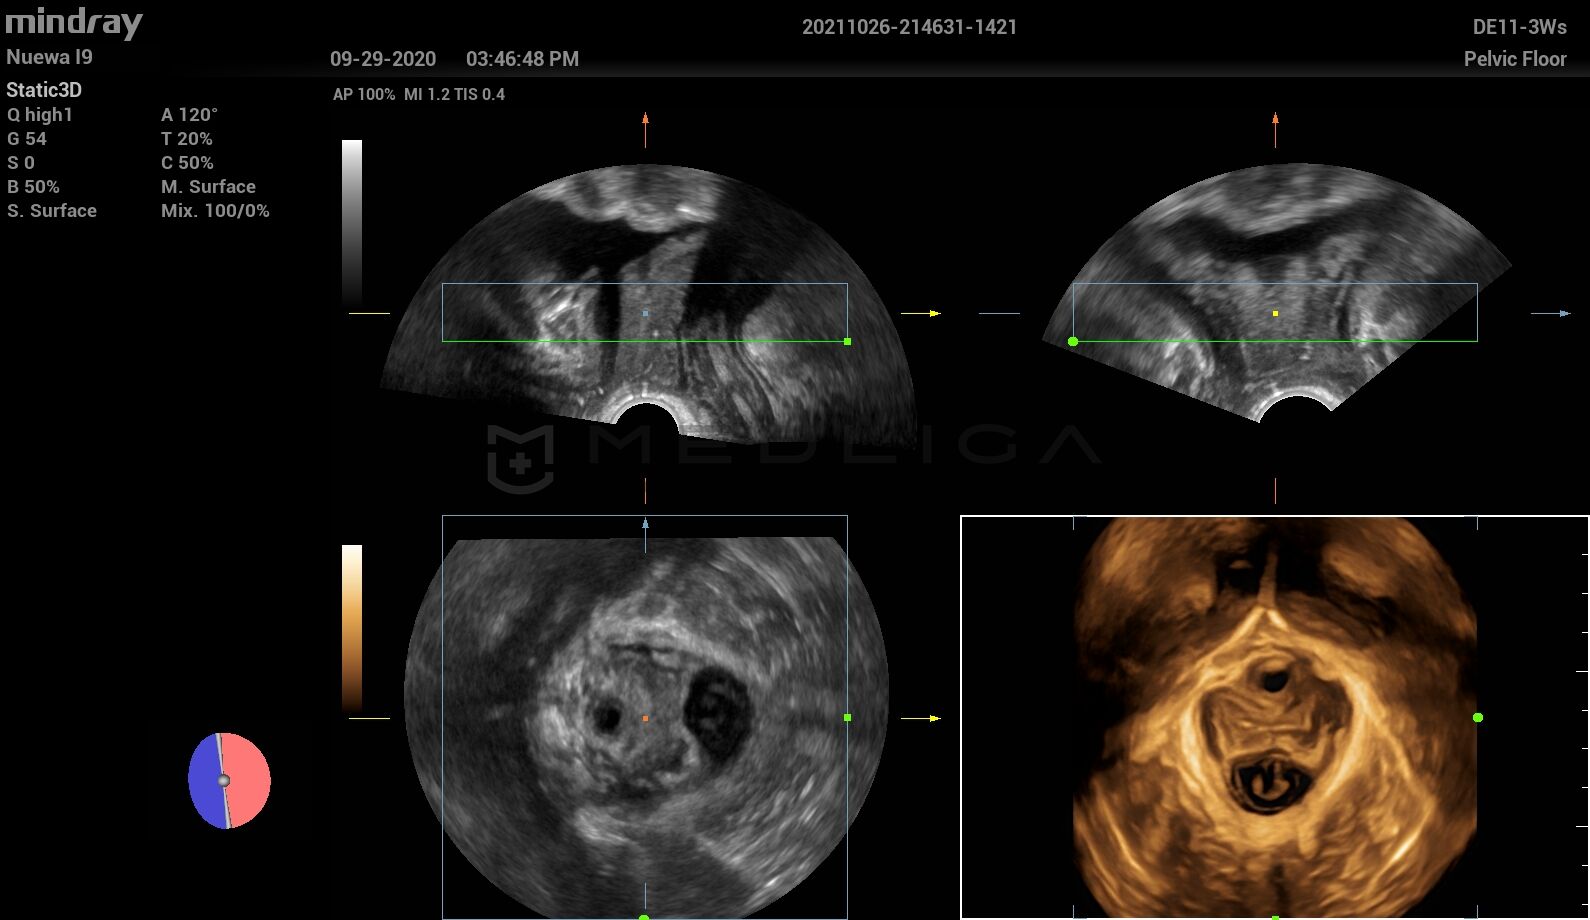

Программное обеспечение для автоматических измерений параметров и оценки функции мышц тазового дна.

Smart Pelvic - новое решение, позволяющее значительно упростить диагностическую процедуру и свести к минимуму время исследования функций мышц тазового дна. Благодаря чрезвычайно простому пользовательскому интерфейсу, программа генерирует стандартную систему координат и автоматически просчитывает все связанные измерения в течение нескольких секунд.